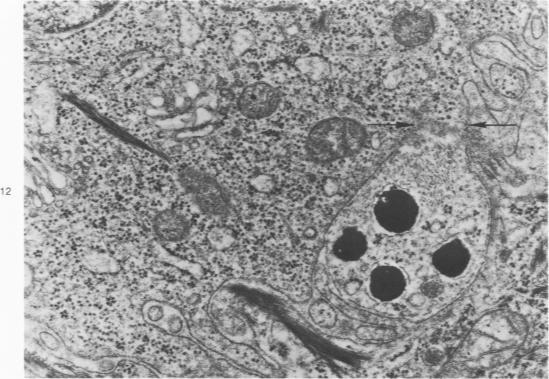

Melanin pigmentation of the corneal epithelium was induced in pigmented guinea pigs by the topical application of colchicine to their eyes or by corneal cauterization with silver nitrate. With colchicine the pigmentation was preceded by the development of an abnormal corneal epithelium in which numerous cells became arrested in cell division. The corneal melanosis resulted largely from the migration of melanocytes into the corneal epithelium from the normally pigmented contiguous conjunctiva and to a lesser extent from the presence of melanin granules within corneal epithelial cells. In both models a leukocytic and vascular invasion of the cornea proceded and accompanied the migration of melanocytes into the corneal epithelium. Electron microscopy disclosed cells with the same morphology as conjunctival melanocytes between the epithelial cells of the cornea. Mature melanin granules were also present within some squamous epithelial cells as individual granules or as clusters. The ultrastructural findings are viewed in relation to how melanin granules are transferred from melanocytes to epithelial cells. Evidence is presented which suggests that malanin granule transfer may follow the fusion of the membranes of the melanocytes and epithelial cells.

通过向有色豚鼠的眼睛局部应用秋水仙碱或用硝酸银进行角膜烧灼,可诱导角膜上皮的黑色素沉着。使用秋水仙碱时,色素沉着之前会出现异常的角膜上皮,其中许多细胞在细胞分裂中停滞。角膜黑变病主要是由于黑素细胞从正常色素沉着的相邻结膜迁移到角膜上皮,在较小程度上是由于角膜上皮细胞内存在黑色素颗粒。在这两种模型中,角膜均出现白细胞和血管浸润,并伴随黑素细胞迁移到角膜上皮。电子显微镜检查发现角膜上皮细胞之间存在与结膜黑素细胞形态相同的细胞。成熟的黑色素颗粒也以单个颗粒或簇的形式存在于一些鳞状上皮细胞内。结合黑色素颗粒如何从黑素细胞转移到上皮细胞来观察超微结构的发现。有证据表明,黑色素颗粒转移可能发生在黑素细胞和上皮细胞膜融合之后。